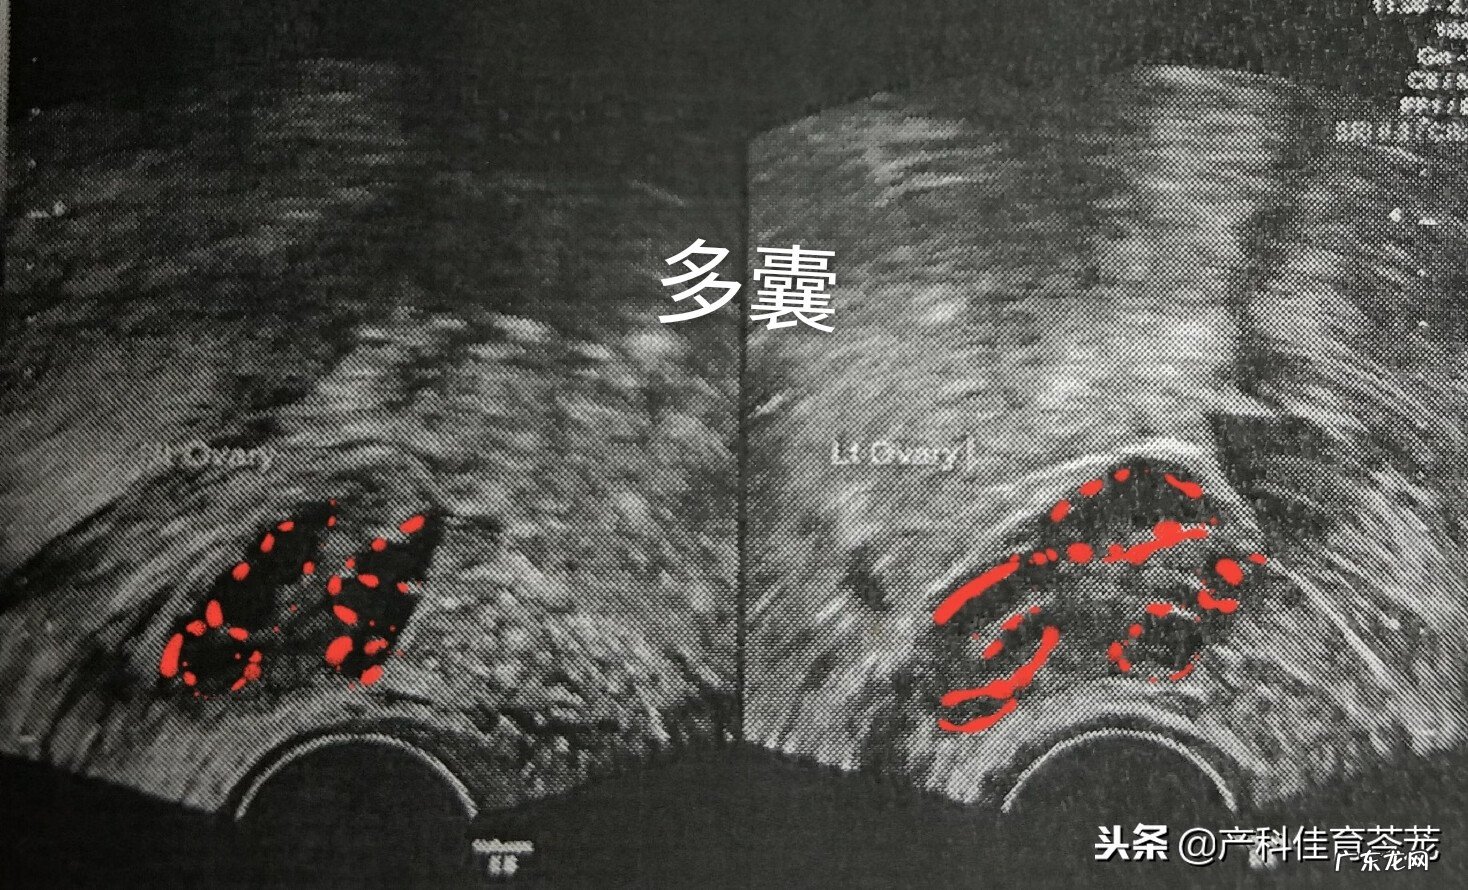

同样是卵巢增大,但B超图像是这样的:

文章插图

可以看到卵巢内有很多个黑色的区域,专业术语称为“液性暗区”,其实是多了卵泡 。